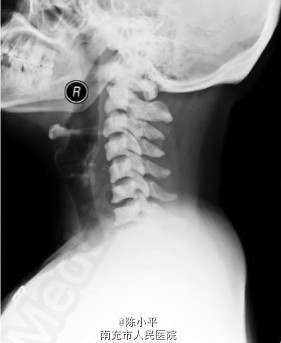

氟骨症一例

氟骨症

患者女,37岁,颈部不适检查时发现,加拍骨盆片,可见纱布眼状骨纹理,未见“同心环”影及腰椎“夹心蛋糕”征,结合职业史,诊断为氟骨症。